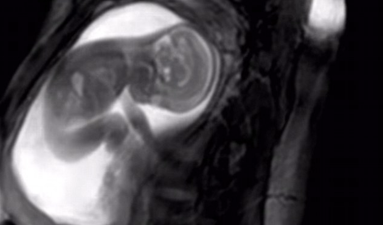

New MRI scan lets parents see their babies in AMAZING detail inside the womb

By Trine Jensen-Burke